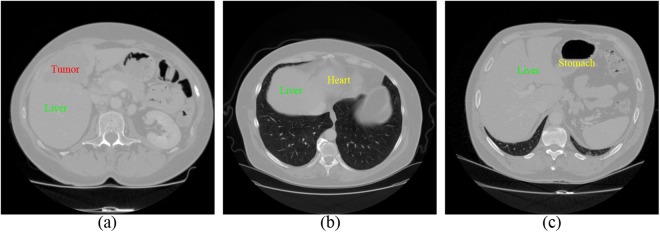

However, some factors in CT images bring some challenges to liver segmentation. First, imaging artifacts and tumor pathologies often result in intensity inhomogeneity. Therefore some standard approaches depending on gray-value only, may not be sufficient for this case. Second, intensities of several adjacent organs like heart and stomach are very similar to liver tissue itself. In Fig. 1, some examples of these difficulties are given. Multi-dimensional features and shape priors can aid to separate the neighboring organs with similar intensities and reach the desired boundaries of the structures.

Figure 1.

Examples of the limiting factors for liver segmentation in CT images. (a) Demonstrates intensity inhomogeneity between liver and tumor. (b) and (c) display that liver, heart, and stomach share similar intensity value.